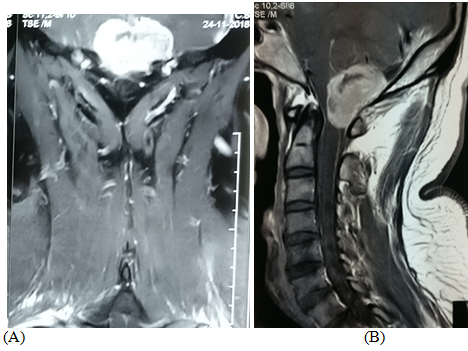

A 25years female admitted in  our department of Neurosurgery with the complaints of neck pain for 1 year, progressive weakness of all limbs in the form of rotating paralysis starting with right upper limb followed by right lower limb, left lower limb & left upper limb for 8months with bowel bladder disturbance in the form of urgency & frequency, on  neurological examination patient was found to be quadri-paretic having muscle power Medical Research Council (MRC)  grade 4 on right side & 3 on left side rendering her gait to be hemiplegic and walk with support. All her deep tendon reflexes were exaggerated with bilateral planter extensor. Ankle clonus was present bilaterally. She did not have any hypo or hyper pigmented patch in any part of the body. Magnetic resonance imaging (MRI) of brain & cervical spine  showed an intra-dural extra-medullary lesion measuring about 3.5 x 2.7cm at  foramen magnum extending both up and down.it was placed more on right side crossed the midline and almost touched the  opposite margin of the foramen magnum. Another intra-dural extra-medullary lesion was also noticed at the level of C4/5 region (Figure 1) & (Figure 2). There was no other lesion on further cranial & spinal screening MRI.

Figure 1 MRI revealed right FM meningioma with 3.5 x 2.7cm

Figure 2 MRI revealed duel pathology at right FM & at C4/5 level.